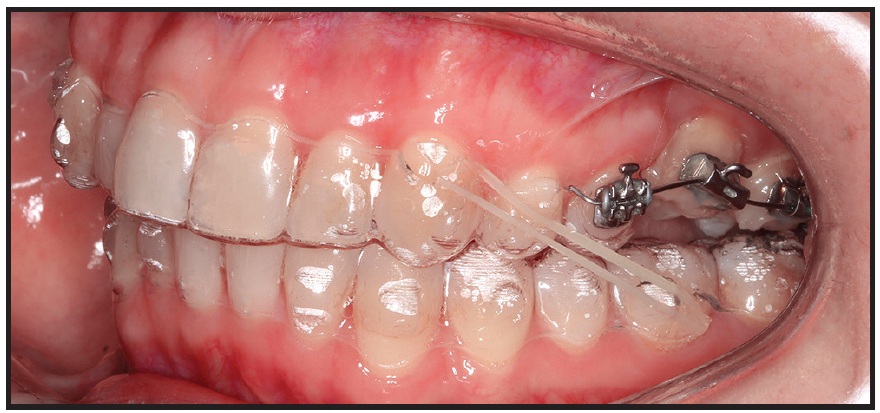

Clinicians can also use partial appliances with clear aligners in the same arch, as is commonly done when treating mesioangular lower second molars. In this instance, the labial appliances are placed only on the premolars and molars for insertion of a segmental nickel titanium wire, while the terminal end of the clear aligner extends just over the most anterior bracketed tooth (Fig. 2). Most recently, anterior lingual appliances have been used underneath full-arch clear aligners to reinforce their prescribed movements (Fig. 3).2

Fig. 3 Lower anterior lingual appliance under overlay clear aligners (photo courtesy of Dr. Luca Lombardo).